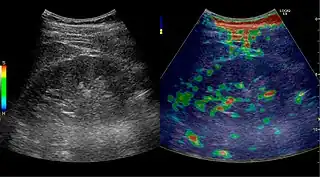

Complex cysts can have membranes dividing the fluid-filled center with internal echoes, calcifications or irregular thickened walls. The complex cyst can be further evaluated with Doppler US, and for Bosniak classification and follow-up of complex cysts, either contrast-enhanced ultrasound (CEUS) or contrast CT is used (Figure 6). The Bosniak classification is divided into four groups going from I, corresponding to a simple cyst, to IV, corresponding to a cyst with solid parts and an 85–100% risk of malignancy.[1] In polycystic kidney disease, multiple cysts of varying size in close contact with each other are seen filling virtually the entire renal region. In advanced stages of this disease, the kidneys are enlarged with a lack of corticomedullary differentiation (Figure 7).[1]